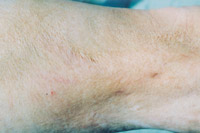

5.深Ⅱ度、浅Ⅲ度混淆度创面(左上臂内侧)自行愈合后3年,,,,,皮肤结构大部分正常

6.浅Ⅲ度创面(背部)自行愈合后3年,,,,,皮肤结构基本正常,,,,,无显着瘢痕

7.浅Ⅲ度创面(右大腿及膝枢纽外侧)自行愈合后3年,,,,,少量瘢痕平整柔软,,,,,无增生,,,,,少量色素缺失,,,,,皮肤弹性好,,,,,不影响功效

8.深Ⅲ度创面(右大腿及膝枢纽内侧)自行愈合后3年,,,,,瘢痕平整柔软,,,,,无挛缩,,,,,不影响功效